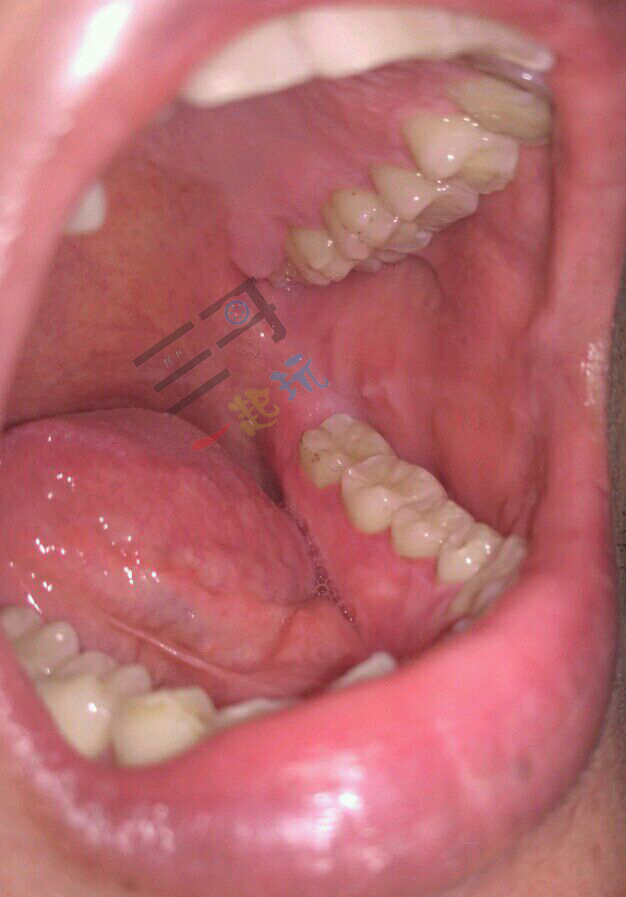

小编洗牙已经过去三个月了,从责任角度讲,有权利讲讲洗牙前后感受了,总体说只有健康没有危害。以下是本人对比照片,本打算拍了自己对比看看,现在为了告诉大家真相,也不怕把自己张嘴拍照的丑态给晾晒出来了。

小编有十年的烟龄,截止洗牙前,已经告捷戒烟两年半了,我确定已经戒掉了,因为偶尔闻到别人抽烟,也觉得呛鼻恶心了。多年的烟垢,努力刷牙两年,也没有完全去除。所以决定彻底清洗一次牙齿。欢迎大家关注我,以后再写写自己戒烟的经历。

洗牙后有个抛光环节,就是拿着镊子,夹着棉花,沾点含有颗粒沙子状的药水,在牙齿上来回的摩擦,抛光药水有点薄荷的清凉。去除了九成牙垢,洗完后多少还有一点。医生说后期刷牙会完全处理掉。